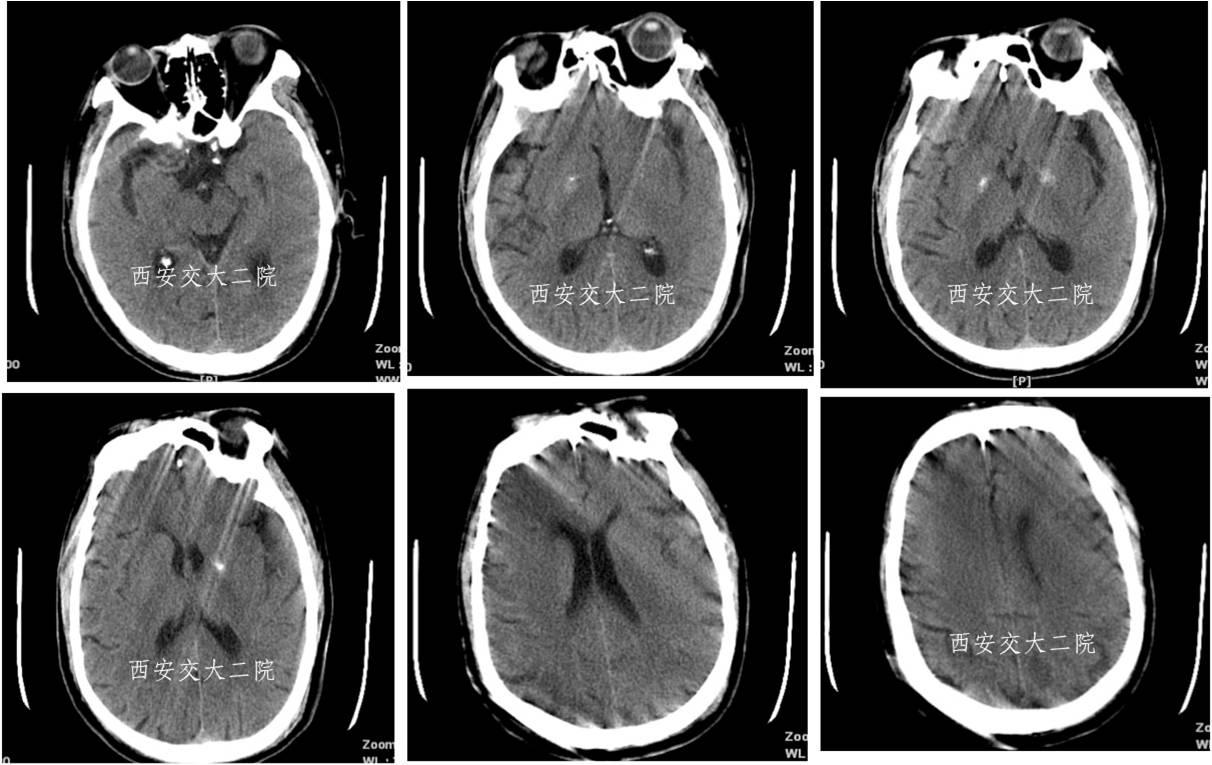

取栓后即刻脑CT及临表

术后24h脑CT及临表

术后4天脑CT及临表

术后2周脑CT及临表